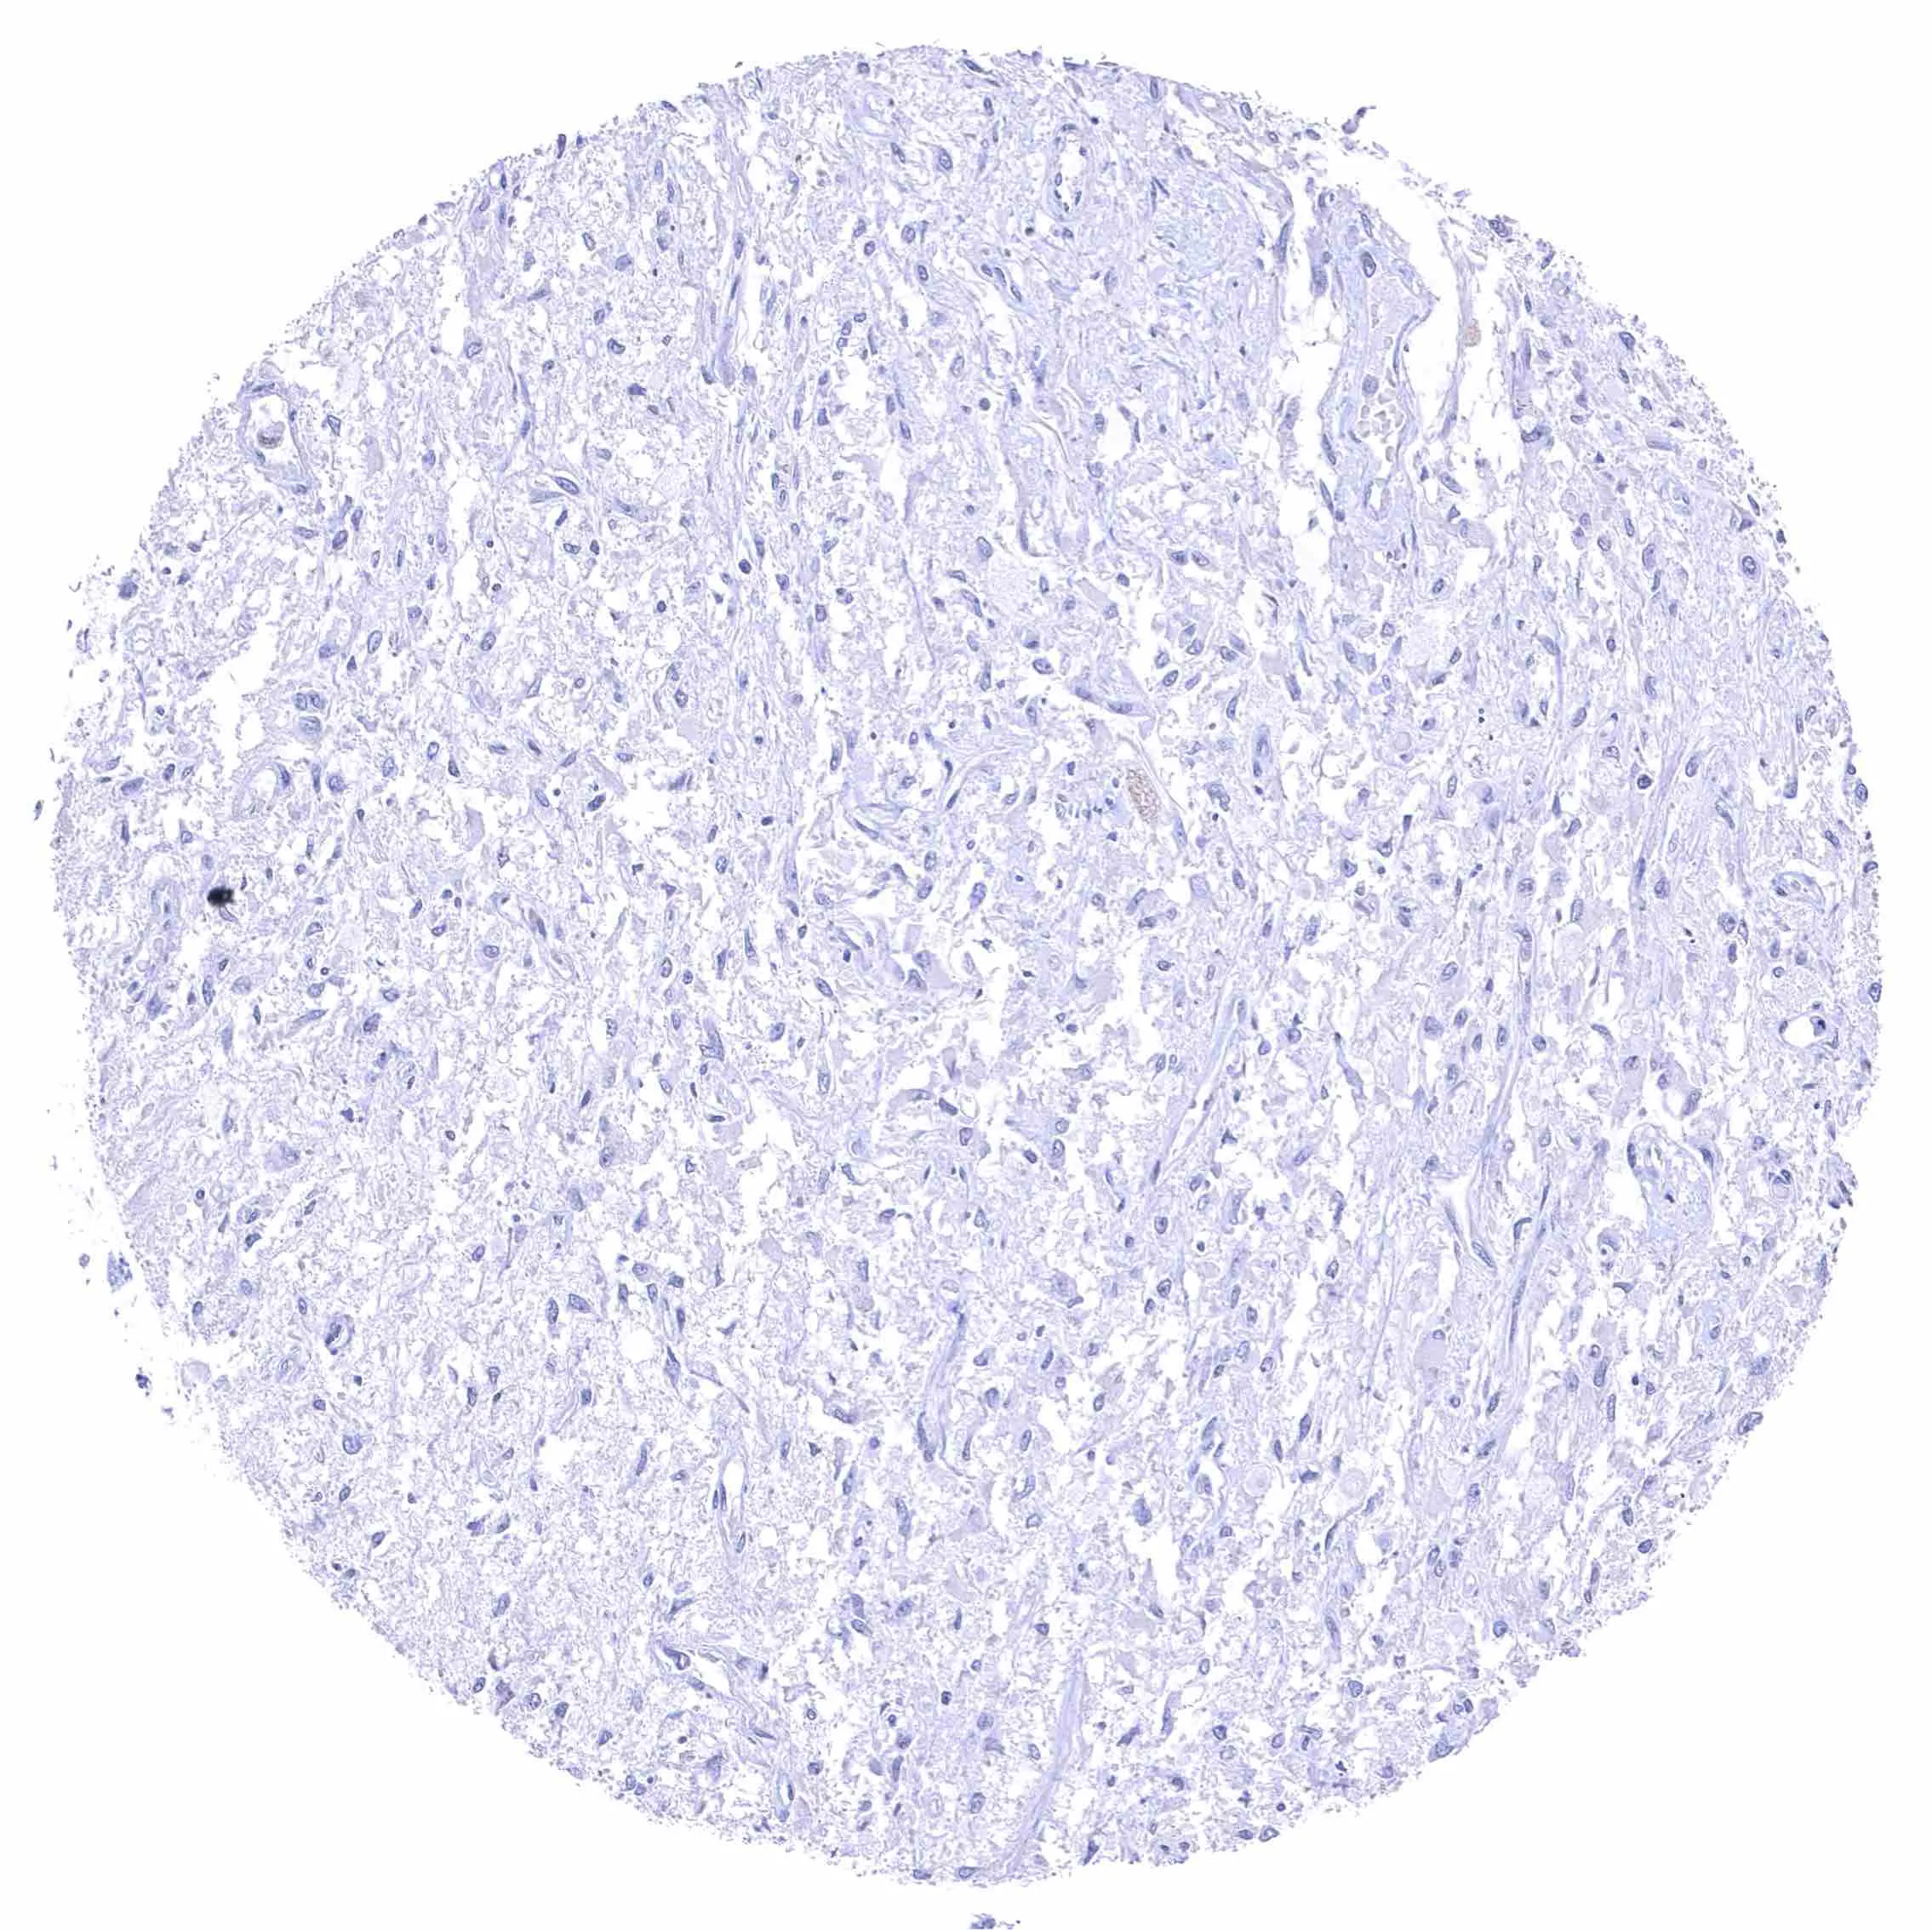

Uterus, myometrium – Distinct NPR-C staining of endothelial cells in some but not all blood vessels